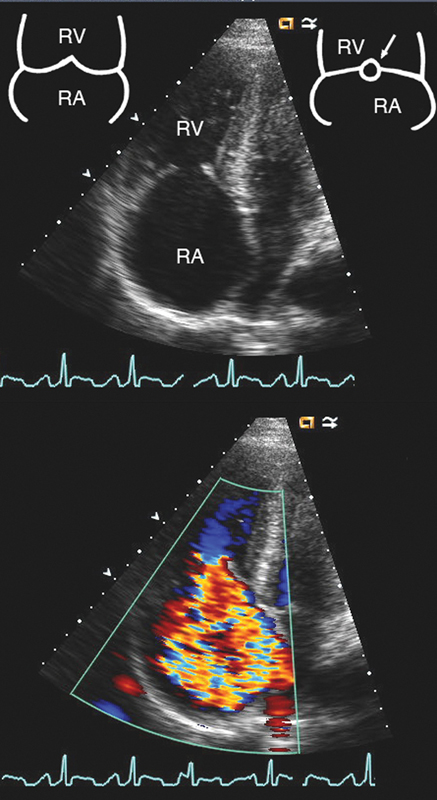

فحوصات تشخيصية لبعض امراض القلب والشرايين التاجية